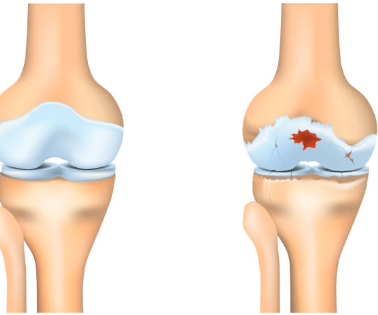

1. 무릎 연골 손상이란 무엇인지부터 쉽게 이해하기

무릎에는 뼈가 서로 부딪히지 않도록 도와주는 “연골”이 있어요.

대표적으로 두 가지가 중요합니다.

첫째, 관절연골

무릎뼈 끝을 매끈하게 감싸서 마찰을 줄여주고 충격을 흡수해요.

둘째, 반월상연골(반달연골)

무릎 안쪽과 바깥쪽에 있는 반달 모양의 연골로, 체중이 한쪽에 쏠리지 않도록 분산해 주는 역할을 해요.

이 연골이 닳거나 찢어지거나 손상되면 무릎이 뻣뻣하고 아프고, 걷는 자세까지 달라지면서 다른 관절까지 무리가 가기 쉬워요.

연골은 혈관이 거의 없어서 “피가 통하면서 빨리 낫는 조직”이 아니에요. 그래서 작은 손상도 그냥 넘기지 말고, 초기에 관리해 줘야 회복이 훨씬 수월합니다.